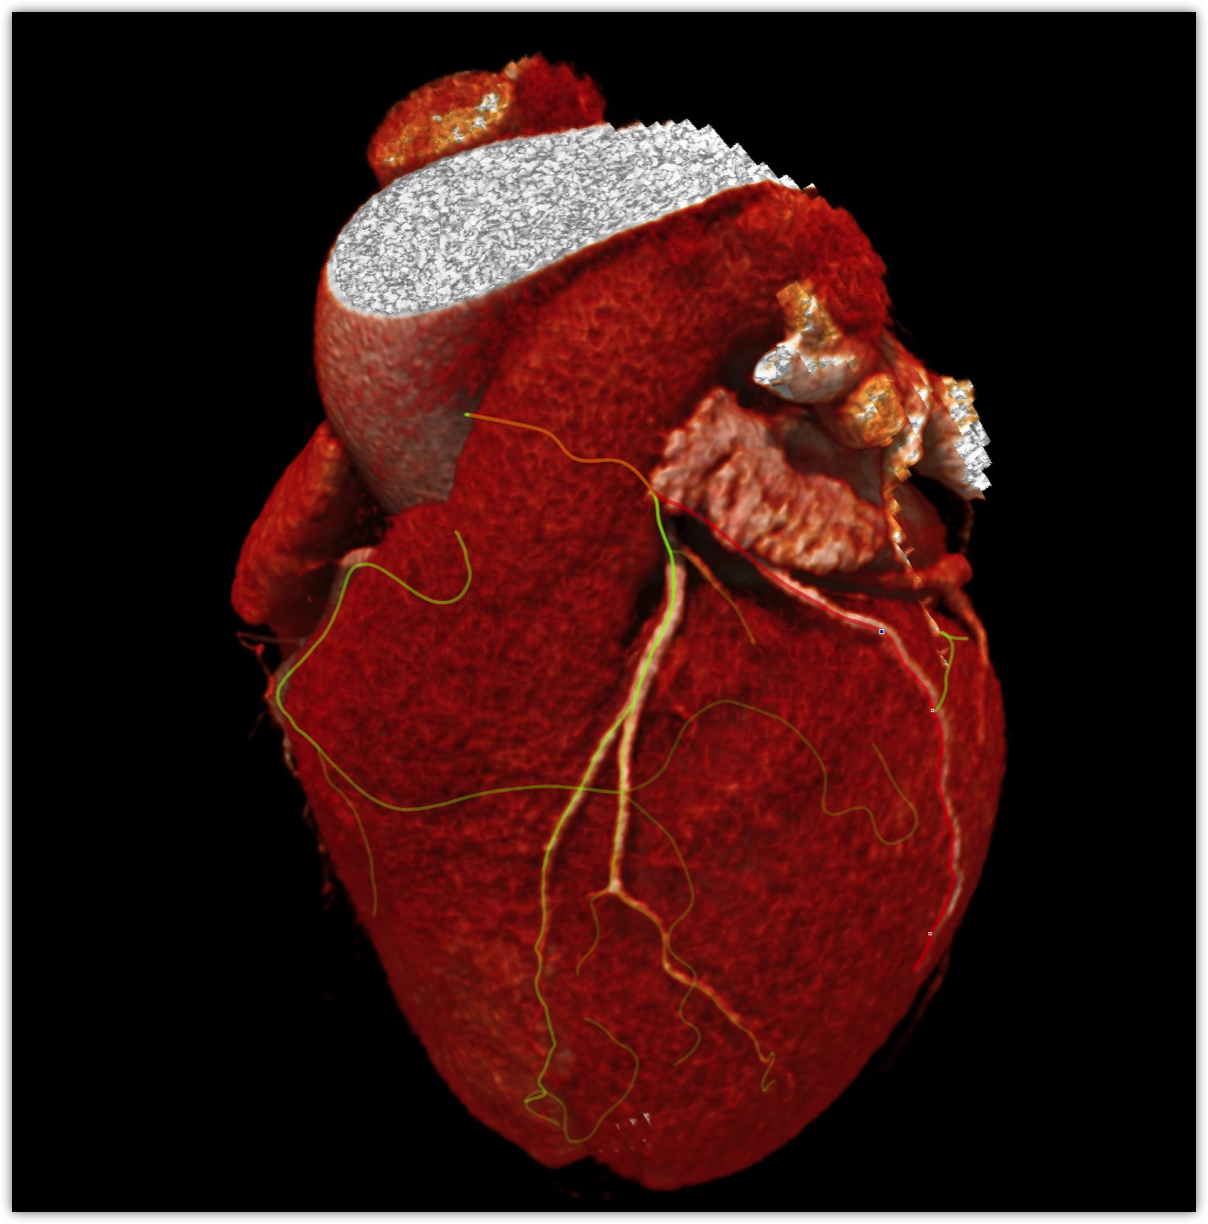

We believe in keeping you as healthy as possible. One of the ways we do this is by checking for heart disease with a Coronary CT Angiogram (CCTA) — a non-invasive scan that can see disease in your heart vessels even if you have no symptoms.

Most people have no symptoms until it’s too late. A Coronary CT Angiogram (CCTA) lets us see disease in the vessels of your heart — before a heart attack happens.

Aorta scan